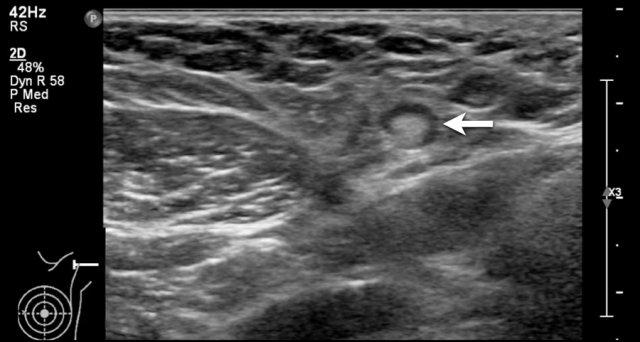

Khối u trong nang

Đôi khi một phần của nang không có hình ảnh trống âm mà lại giảm âm hoặc tăng âm.

Điều này có thể là kết quả của mủ hoặc các mảnh vụn, nhưng cũng có thể là một khối u trong nang như trong các hình ảnh này.

Khối u trong nang là hiếm gặp.

Khi thấy có mạch máu trên siêu âm Doppler màu thì đó là khối u trong nang, có thể lành tính hoặc ác tính.

Đây là một khối u có thành phần dạng nang chứ không phải là một nang đơn thuần.

Trong trường hợp không có dòng chảy trên siêu âm Doppler màu và không có tín hiệu âm mức độ thấp di chuyển khi thay đổi tư thế bệnh nhân, cần thực hiện chọc hút để phân biệt giữa nang phức tạp và khối đặc.

Mủ và các mảnh vụn có thể được hút ra, khác với khối u.

Trong trường hợp này, sinh thiết xác nhận là ung thư biểu mô trong nang.